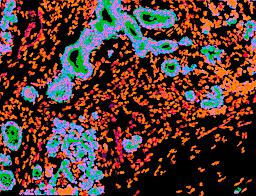

Pancreatic ductal adenocarcinoma is a lethal disease with limited treatment options and poor survival. We studied 83 spatial samples from 31 patients (11 treatment-naïve and 20 treated) using single-cell/nucleus RNA sequencing, bulk-proteogenomics, spatial transcriptomics and cellular imaging. Subpopulations of tumor cells exhibited signatures of proliferation, KRAS signaling, cell stress and epithelial-to-mesenchymal transition. Mapping mutations and copy number events distinguished tumor populations from normal and transitional cells, including acinar-to-ductal metaplasia and pancreatic intraepithelial neoplasia. Pathology-assisted deconvolution of spatial transcriptomic data identified tumor and transitional subpopulations with distinct histological features. We showed coordinated expression of TIGIT in exhausted and regulatory T cells and Nectin in tumor cells. Chemo-resistant samples contain a threefold enrichment of inflammatory cancer-associated fibroblasts that upregulate metallothioneins. Our study reveals a deeper understanding of the intricate substructure of pancreatic ductal adenocarcinoma tumors that could help improve therapy for patients with this disease.